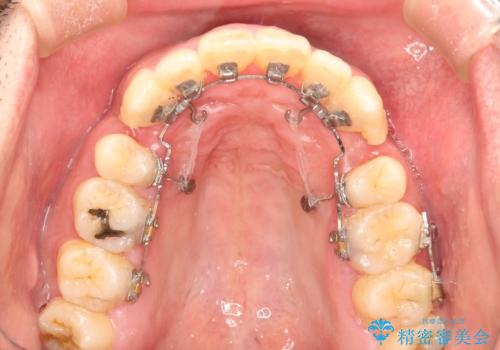

上顎の前から4番目の歯を両側、合計2本抜歯して矯正する計画としました。

目立たない装置がご希望でしたので、上下裏側ワイヤー装置を選択されました。

裏側矯正は目立たないという利点がありますが、歯ブラシが非常に難しいなどのデメリットもあります。